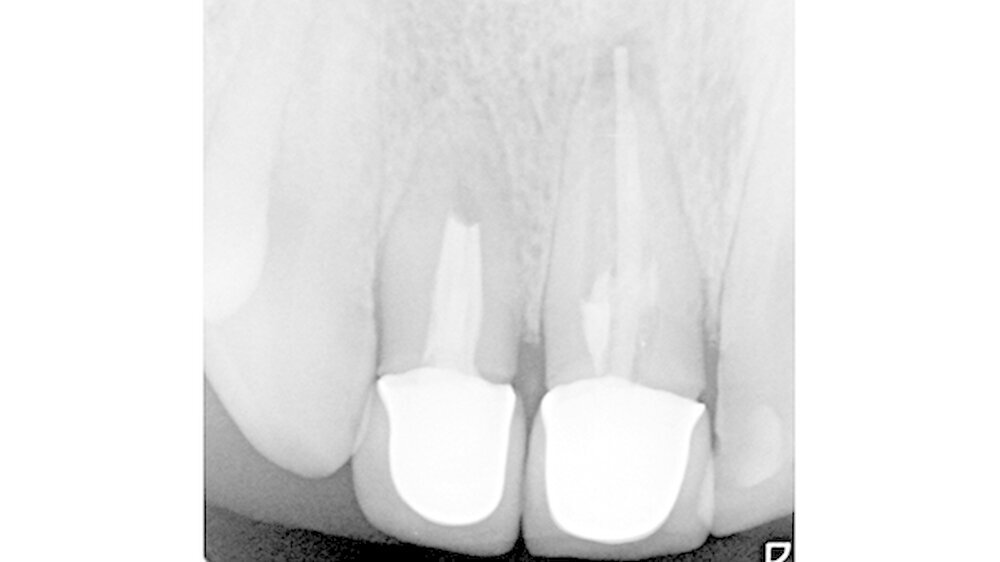

Nach klinischer Befundung und Röntgendiagnostik (Abbildung 2) wurde in der Einzelzahnaufnahme eine insuffiziente über das Foramen apicale hinausgebrachte Wurzelkanalfüllung an 11 festgestellt. Zusätzlich bestand eine periapikale Osteolyse. Zahn 12 war ebenfalls endodontisch versorgt, wobei in der Bildgebung kein Nachweis einer radioopaken Füllung des apikalen Kanaldrittels gelang. Es bestand an 12 keine apikale Osteolyse.

Beide Zähne imponierten radiologisch mit weiten apikalen Foramina sowie verkürzten Wurzeln. Auf Nachfrage gab der Patient ein vor circa 20 Jahren stattgefundenes Frontzahntrauma an. Beide Zähne waren klinisch asymptomatisch. Dem Patienten wurden der klinische und röntgenologische Befund erörtert und die Behandlungsoptionen aufgezeigt.